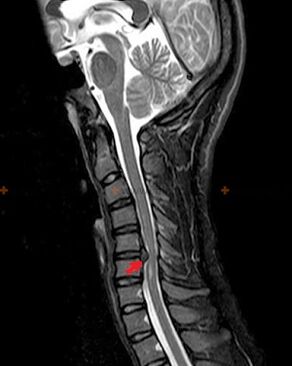

Diagnostics et signes radiologiques

L'ostéochondrose est un diagnostic radiologique, car un tableau clinique détaillé n'est disponible qu'au moment de l'exacerbation, tandis que des modifications de la colonne vertébrale peuvent survenir avec le bien-être subjectif complet d'une personne. Sans examen aux rayons X, nous ne pouvons parler que d'une suspicion d'ostéochondrose, car des symptômes similaires peuvent être provoqués par d'autres maladies (myosite, néoplasmes vertébraux et autres).

Pour diagnostiquer l'ostéochondrose, les méthodes de recherche suivantes sont utilisées : radiographie (de préférence avec tests fonctionnels), MSCT et IRM. Cette dernière étude est la plus préférable car elle permet de visualiser très clairement l'état des structures intervertébrales.

Les signes radiologiques de l'ostéochondrose comprennent les modifications suivantes dans la colonne vertébrale :

- Hauteur réduite des disques intervertébraux.

- Présence d’excroissances osseuses marginales.

- Violation de l'emplacement des vertèbres les unes par rapport aux autres.

- Déformations des corps vertébraux et des arcs vertébraux, etc.

La présence des changements décrits ci-dessus, ainsi que des changements dans la structure du disque intervertébral, détectés par MSCT et IRM, constituent des signes fiables confirmant la présence d'ostéochondrose.